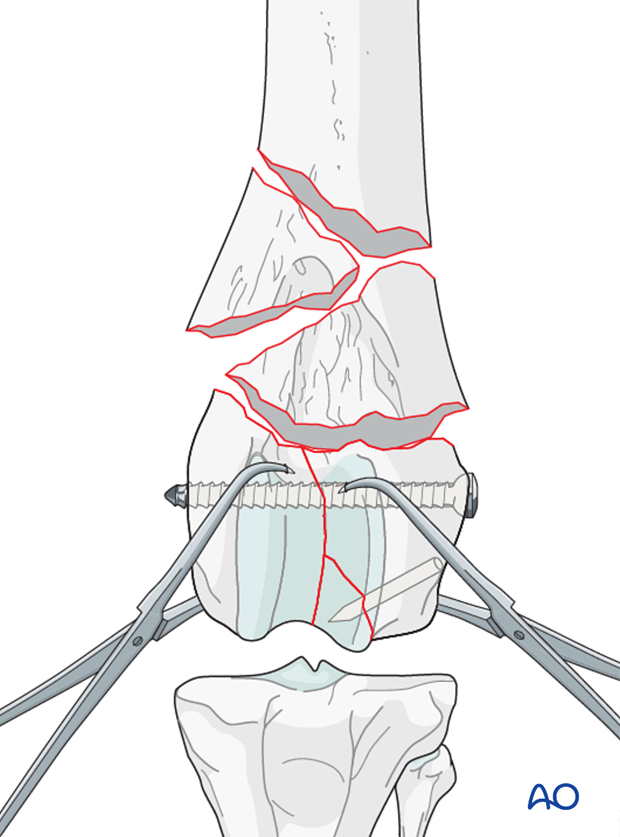

Interfragmentary compression is achieved with a lag screw for anatomical reduction of the articular fracture.

Stabilization is achieved with inserting a screw in lag fashion across the condyles perpendicular to the fracture plane. Frequently the screw is placed in lateral to medial direction, starting at the level of the epicondyle.

Note: Care should be taken not to penetrate the condylar fossa to avoid damage to the cruciate ligaments with the screw.

A detailed description of "Lag screw fixation" can be found here.

Definitive stabilization of the smaller fragments of the condyles may be performed using lag screws or K-wires.

Note: If the screw head or K-wire is positioned in the articular surface they must be countersunk to avoid interference with intraarticular structures.